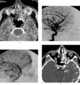

Ethmoid sinus cancer

The ethmoid sinuses or ethmoid air cells of the ethmoid bone are one of the four paired paranasal sinuses. The cells are variable in both size and number in the lateral mass of each of the ethmoid bones and cannot be palpated during an extraoral examination. [Source: Wikipedia ]